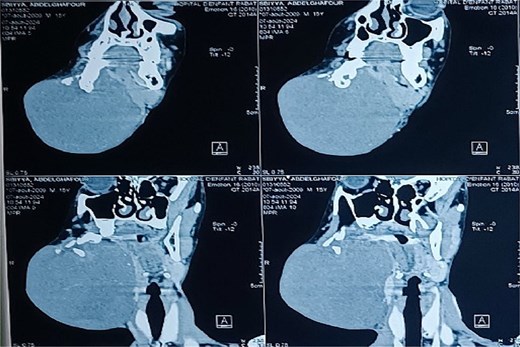

Panoramic radiography showed a well-defined radiolucent lesion involving the right mandibular angle and ramus. Coronal computed tomography (CT) scan in soft tissue window demonstrating a well-defined osteolytic mandibular lesion (12 × 9 × 14 cm) with cortical thinning (Figs 3 and 4).

Coronal CT scan in soft tissue window demonstrating a well-defined osteolytic mandibular lesion with cortical thinning.